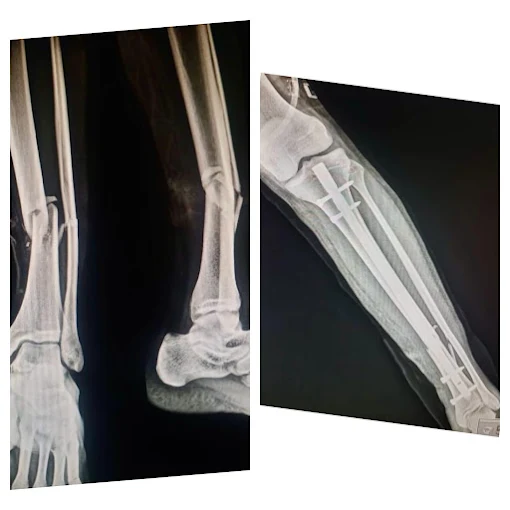

Trauma Surgery

Expert fracture and bone injury management with advanced surgical care

Bone Fracture Treatment

Specialized treatment and bone healing for all types of fractures

Fracture & Trauma Surgery

Expert management for complex fractures and trauma recovery

Fracture and accident care

Specialized care for accident-related bone and joint injuries